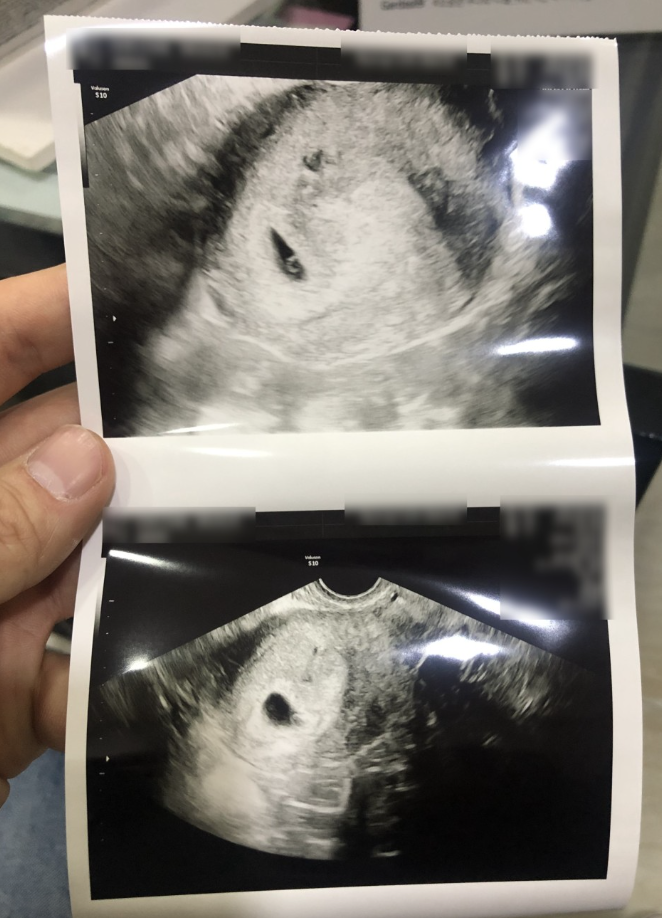

스크린샷 2022-10-17 오전 10.49.32.png 이랬던 네가 하나의 생명이 되어 태어나다니!